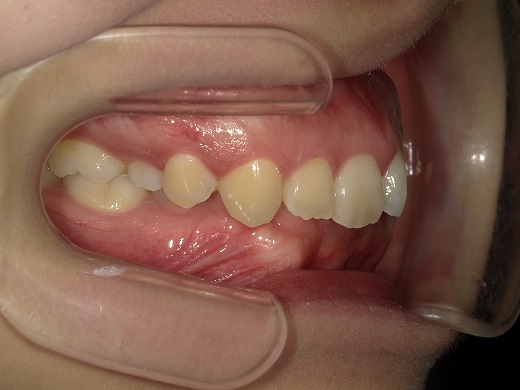

治療前右側

治療中右側

治療後右側